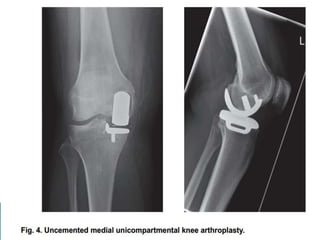

 Surgical option for knee arthritis when only one compartment of

the knee is involved.

 Epidemiology

◦ 5% of surgeries where knee arthroplasty is indicated

are unicompartmental knee replacements

◦ location

 fimedial compartment is most common

 Types of implants

◦ fixed-bearing

 historical standard of care

◦ mobile-bearing

 pros

 weightbearing through the meniscus increases conformity and contact

without increasing constraint

 decrease in wear pattern

 excellent survivorship out to the second decade

 cons

 technically demanding

 bearings can dislocate